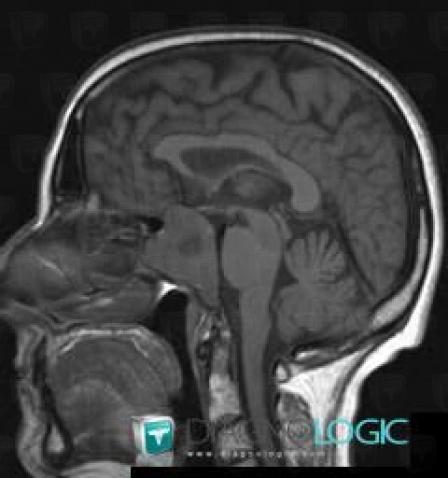

Macroadénome hypophysaire, Hypophyse et région parasellaire, IRM

Voici les informations spécifiques à l'image clé ci dessus:

- Diagnostic Macroadénome hypophysaire, Localisation(s) Hypophyse et région parasellaire, comportant les gammes Lésion en hypersignal T2 sellaire ou parasellaire